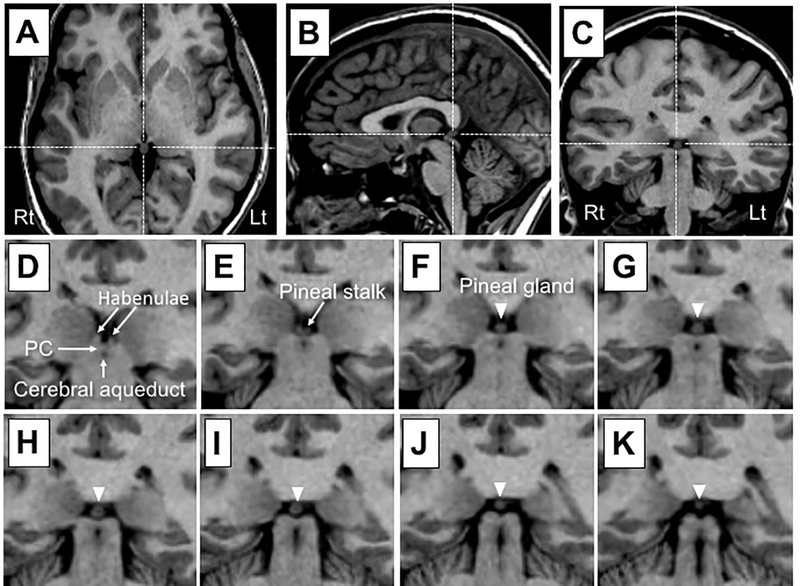

Pineal gland là gì? Tuyến tùng quả, hay Pineal gland, là một tuyến nội tiết nhỏ đặt trong hệ thống thần kinh. Bộ phận này thường được tìm thấy trong não của các loài động vật có xương sống, đặc biệt là ở vùng biểu mô gần trung tâm não, nằm giữa hai bán cầu và thường được giấu kín trong một rãnh, nơi mà hai mảnh của đồi thị (thalamus) giao nhau. Hình dạng của tuyến tùng giống như một quả tùng nhỏ, nằm gần trung tâm của não và chui vào rãnh nơi hai đồi não gặp nhau. Tuyến tùng chủ yếu chứa các tế bào pinealocytes, chúng chủ yếu sản xuất hormone melatonin, cùng với các tế bào thần kinh đệm, một loại tế bào não đặc biệt, hỗ trợ truyền thông tin trong não.